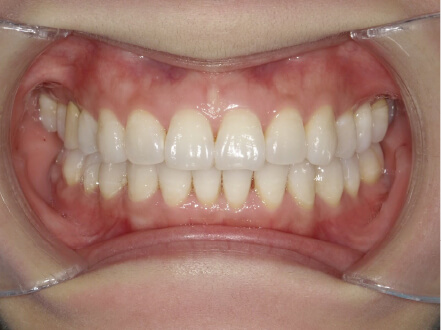

過蓋咬合の症例

15歳

/

女性

相談内容

前歯と前歯が噛んでいない

カウンセリング・診断結果

過蓋咬合

治療内容・方法

全額アライナー矯正

術後の経過・現在の様子

クリアライナー使用

治療のリスク

痛み・歯根吸収・歯肉退縮・虫歯・後戻り

費用・治療期間

830,000円、2年